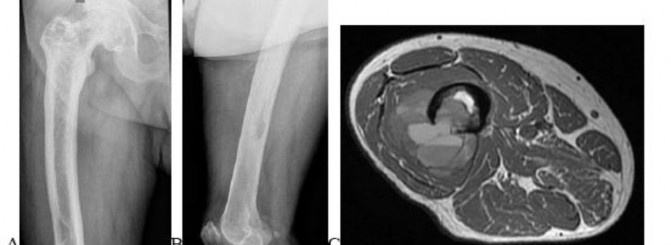

A 15-year-old male presents with deep knee pain awakening him at night. Radiographs show a permeative destructive lesion in the distal femoral metaphysis with a 'sunburst' periosteal reaction and Codman's triangle.

Biopsy confirms high-grade conventional osteosarcoma. What is the most critical prognostic factor for long-term overall survival in this patient?

Explanation

For localized high-grade osteosarcoma, the most important prognostic indicator is the histologic response to neoadjuvant chemotherapy. This is evaluated during the definitive resection. A 'good response' is typically defined as greater than 90% or 99% tumor necrosis. Patients who achieve this level of necrosis have a significantly improved disease-free and overall survival rate compared to 'poor responders' who have extensive viable tumor cells remaining.